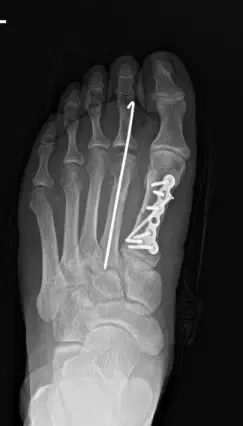

Preoperative Imaging

An X-ray of the right foot confirmed fractures of the first and second metatarsals.

The fractures were reduced and temporarily stabilized with K-wires.

Definitive fixation was achieved using titanium plates and screws.

Fluoroscopic imaging confirmed anatomic alignment and stable fixation.

Postoperative internal fixation with plate and screws of a fracture of the first metatarsal.